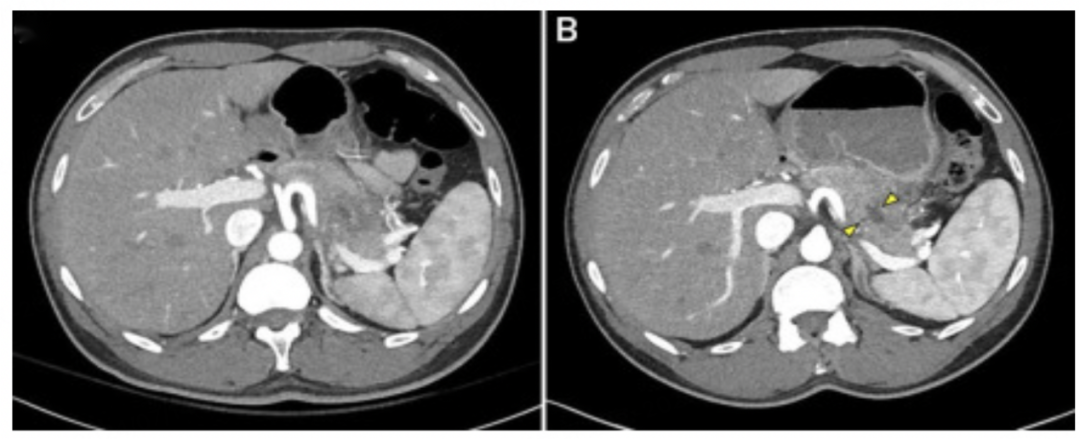

腹部/骨盆计算机断层扫描(CT)示:患者曾行胆囊切除术,胆管正常,胰腺尾部出现条索影和水肿(图1)。结合患者最近的MRCP,这些影像学发现与急性加重的慢性胰腺炎一致。

图1.初次就诊当天腹部/骨盆CT结果